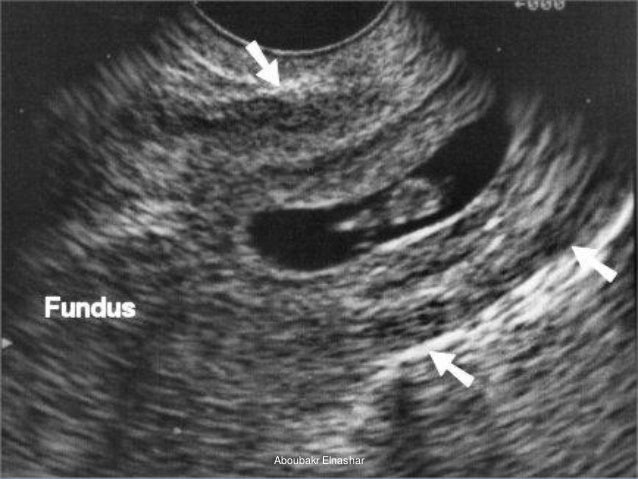

УЗИ: маточная и внематочная беременность